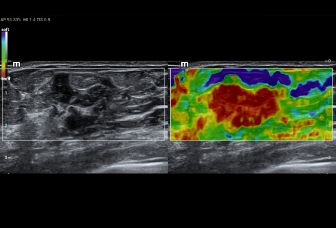

–Ē–ł–į–≥–Ĺ–ĺ—Ā—ā–ł–ļ–į –ĺ—á–į–≥–ĺ–≤—č—Ö –Ņ–ĺ—Ä–į–∂–Ķ–Ĺ–ł–Ļ —Ā –Ņ–ĺ–ľ–ĺ—Č—Ć—é –ļ–ĺ–Ĺ—ā—Ä–į—Ā—ā–ĺ–≤: –ļ–ĺ–Ĺ—ā—Ä–į—Ā—ā-—É—Ā–ł–Ľ–Ķ–Ĺ–Ĺ–į—Ź –≤–ł–∑—É–į–Ľ–ł–∑–į—Ü–ł—Ź UWN+

–ė—Ā–Ņ–ĺ–Ľ—Ć–∑–ĺ–≤–į–Ĺ–ł–Ķ –ļ–į–ļ –≤—ā–ĺ—Ä–ĺ–Ļ –≥–į—Ä–ľ–ĺ–Ĺ–ł–ļ–ł, —ā–į–ļ –ł –Ĺ–Ķ–Ľ–ł–Ĺ–Ķ–Ļ–Ĺ—č—Ö —Ą—É–Ĺ–ī–į–ľ–Ķ–Ĺ—ā–į–Ľ—Ć–Ĺ—č—Ö —Ā–ł–≥–Ĺ–į–Ľ–ĺ–≤

–í—č—Ā–ĺ–ļ–į—Ź —á—É–≤—Ā—ā–≤–ł—ā–Ķ–Ľ—Ć–Ĺ–ĺ—Ā—ā—Ć –ļ –Ĺ–ł–∑–ļ–ĺ–į–ľ–Ņ–Ľ–ł—ā—É–ī–Ĺ—č–ľ —Ā–ł–≥–Ĺ–į–Ľ–į–ľ –ł –Ī–ĺ–Ľ—Ć—ą–Ķ–Ķ –≤—Ä–Ķ–ľ—Ź –Ņ–Ķ—Ä—Ā–ł—Ā—ā–Ķ–Ĺ—Ü–ł–ł –ļ–ĺ–Ĺ—ā—Ä–į—Ā—ā–Ĺ–ĺ–≥–ĺ –≤–Ķ—Č–Ķ—Ā—ā–≤–į

–ö–£–£–ó–ė: –ľ–Ķ—ā–į—Ā—ā–į—ā–ł—á–Ķ—Ā–ļ–ł–Ļ —Ä–į–ļ –Ņ–Ķ—á–Ķ–Ĺ–ł

–ö–£–£–ó–ė: –Ņ–Ķ—Ä—Ą—É–∑–ł—Ź –į–ī–Ķ–Ĺ–ĺ–ľ—č —Č–ł—ā–ĺ–≤–ł–ī–Ĺ–ĺ–Ļ –∂–Ķ–Ľ–Ķ–∑—č